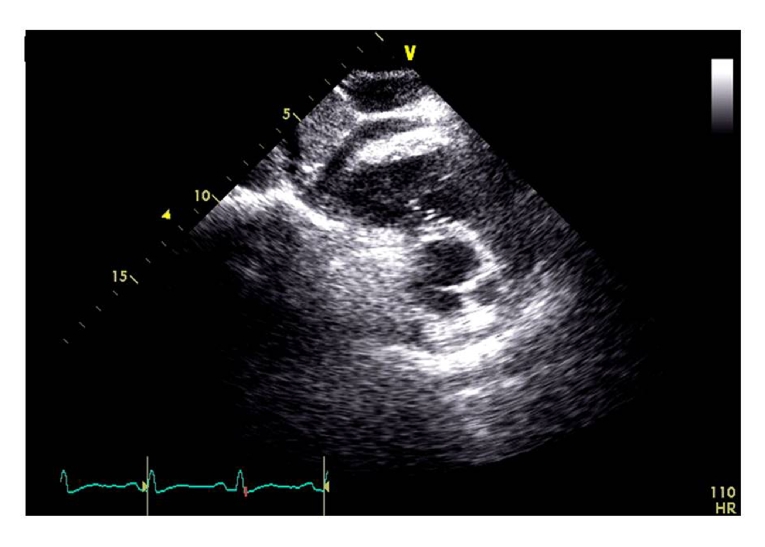

Alternatively, the use of global longitudinal strain (GLS) by speckle tracking echocardiography is strongly recommended [1,2] because of its optimal feasibility and biological reproducibility (about 6%) [6]. Baseline measurements of GLS identify those at high risk of CTRCD in patients undergoing anthracyclines [7]. Moreover, while a relative percentage reduction of GLS <8% from baseline cannot be considered clinically relevant, a GLS reduction from baseline >15% is very likely to be abnormal and could be utilised as the starting point for timely cardioprotection (i.e., beta-blockers and ACE inhibitors) [1]. This strategy could be used in clinical practice to avoid the progression from subclinical CTRCD to overt heart failure in cancer patients, despite the lack of a definite demonstration of its beneficial impact on decision making in this clinical setting. In addition, because of the recognised vendor dependence of speckle tracking echocardiography, the same vendor-specific ultrasound machine should be used for serial determination of GLS in cancer patients [1]. Figure 1 shows a significant drop of GLS (>15% in comparison with baseline values) in a woman with breast cancer during trastuzumab therapy, in the absence of heart failure symptoms. This drop suggests a timely start of cardioprotection in order to avoid the progression of subclinical CTRCD towards overt heart failure.

Figure 1. Changes of LVEF and GLS during chemotherapy in a woman with breast cancer. After the end of EC (epirubicine + cyclophosphamide) cycles, LVEF is still normal but GLS shows a 16% drop from baseline. At this point the patient is asymptomatic but could start cardioprotective therapy according to ASE/EACVI Expert Consensus [1].